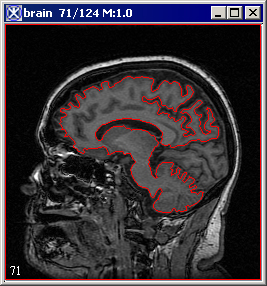

VOI > Evolve Boundary 2D > Active GVF. The Evolve Boundary dialog box uses a special type of active contours, or snakes to find the object boundaries. GVF or the gradient vector flow snake, which is used to calculate VOI boundaries, begins with the calculation of a GVF field of forces by applying generalized diffusion equations to both components of the gradient of an image edge map. Here, GVF fields, are dense vector fields derived from images by minimizing a certain energy functional in a variational framework. The minimization is achieved by solving a pair of decoupled linear partial differential equations that diffuses the gradient vectors of a gray-level or binary edge map computed from the image. See also Figure 3.

Figure 3. An initial VOI (A) and VOI after applying the Evolve Boundary > Active Contour algorithm with the default parameters (B)

A

B